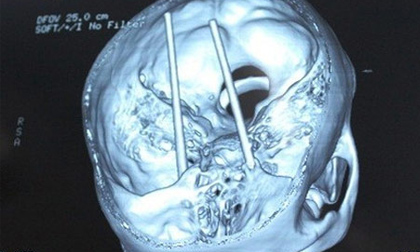

Mâu thuẫn, xuyên đôi đũa qua 2 mắt bạn nhậu

Thấy bạn nhậu bình luận và chê những hình xăm trên người mình, Tưởng dùng đôi đũa xuyên qua 2 mắt anh ta.

Nghi án thanh niên bị đối thủ đâm 2 chiếc đũa xuyên qua mắt

Khi bắt kịp anh Dũng, nhóm thanh niên này dùng 2 chiếc đũa lần lượt đâm vào hốc mắt và dí mạnh cho đến khi...